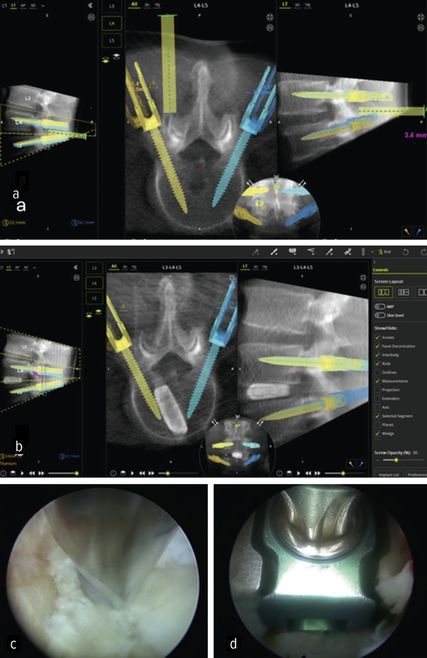

Die minimalinvasive transforaminale lumbale interkorporelle Fusion (Minimally Invasive Transforaminal Lumbar Interbody Fusion; MIS-TLIF) hat in den letzten Jahren an Bedeutung gewonnen, die aufgrund des geringeren Gewebetraumas mit einer früheren Rekonvaleszenz verbunden ist.24 Aus den gleichen Gründen rückt die endoskopische transforaminäre InterbodyFusion (Endo-TLIF) in den Fokus der Aufmerksamkeit. Endo-TLIF ist eine Erweiterung der MIS-TLIF und erfordert eine unilaterale Resektion des Facettengelenkes. Die Grund- und Deckplattenpräparation gilt als entscheidender Faktor, der die Fusionsrate beeinflusst.24 Die Möglichkeit, unter klarer endoskopischer Sicht die Endplatten präzise darzustellen, erlaubt eine ideale Aufbereitung des Fusionsbettes. Dies könnte zu einer Erhöhung der Fusionsrate beitragen. Zudem profitieren die Patienten durch eine raschere Erholung, einen geringeren Opioidbedarf, eine frühzeitige Mobilisierung und eine verkürzte stationäre Verweildauer.25 Limitationen liegen aktuell bei höhergradigen Listhesen und kollabierten Bandscheibenräumen vor.26 Um das Potenzial der Methodik zu untermauern, bedarf es robuster Studien mit erhöhtem Evidenzlevel sowie eines einheitlichen Standards der endoskopischen Fusionstechniken. Abbildung 6 zeigt eine Planungsanwendung (MazorX® Application, Fa. Medtronic) für Endoskoptrajektorie und Pedikelschraubenimplantation im Rahmen der Endo-TLIF-Operation (a, b). Abbildung b zeigt einen oblique eingebrachten Cage (eFuse® expandable, Fa. Evospine), Abbildung c einen Nukleusresektor (Fa. RIWOspine) bei Präparation des Fusionsbettes. Abbildung d zeigt, dass eine Cagedistraktion unter direkter Sicht möglich ist.

Quillo-Olvera et al. zeigten, dass die intraoperative Navigation die Sicherheit der Pedikelschraubenfixation und die präzise Endoskoppositionierung bei TLIF verbessert.33 Klassische Navigationssysteme erfordern optische Marker, die im Operationsgebiet zusätzlichen Platz benötigen. Dieser Einschränkung kann unter Verwendung elektromagnetischer Navigationssysteme (EMN) bei vollendoskopischen Verfahren begegnet werden.33 Randomisierte Studien mit EMN weisen eine geringere Strahlenbelastung und signifikante Reduktion der Operationszeit auf.34 Zukünftig bieten diese Systeme das Potenzial, die Sicherheit zu erhöhen und gleichzeitig die Lernkurve abzukürzen. Abbildung 8 zeigt ein intraoperatives Setup während Endo-TLIF-Operation mit integriertem O-Arm (Fa. Medtronic), navigationsgestütztem Robotersystem (MazorX®) und Endo-Turm mit Funktionseinheiten (Fa. RIWOspine) (a, b). Darüber hinaus illustriert sie eine transforaminäre Diskektomie unter Verwendung des elektromagnetischen Navigationssystems (RIWOtrack®, Fa. RIWOspine) mit Abbildung des Multipads zur Instrumentenkalibrierung (c), EMN mit dargestellten Referenzmarkern und Endoskopiebild (d).

Höhere Genauigkeit, kürzere Krankenhausaufenthalte und geringere Strahlenexposition sind die Gründe für den Einsatz bei der Pedikelschrauben-Implantation.32 Zusätzlich bieten sie den Vorteil der exakten physischen Führung, um präoperativ geplante chirurgische Trajektorien in der Endoskoppositionierung umzusetzen. Wang et al. setzten robotische Assistenz bei vollendoskopischen lumbalen Diskektomien ein und konnten Sicherheit und Effektivität als Alternative zur konventionell fluoroskopischen ESS bestätigen.38 Im eigenen Haus wurde das Verfahren bei der endoskopischen TLIF-Operation angewandt.